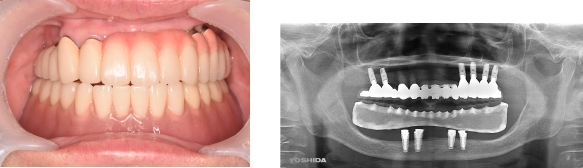

インプラント症例③ ~ほとんど歯が無い例~

●残っている歯が2本しかなく、上下、入れ歯を何度と作っているが、全然合わない。

●上にはインプラントを6本入れて、固定式の歯を入れました。

●下にはインプラントを4本入れて、マグネットを取り付けて、安定する入れ歯にしました。